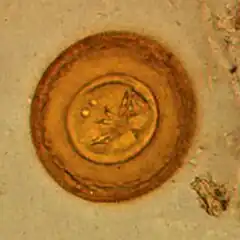

-

Egg of H. diminuta in a wet mount(stained with iodine)[17] -